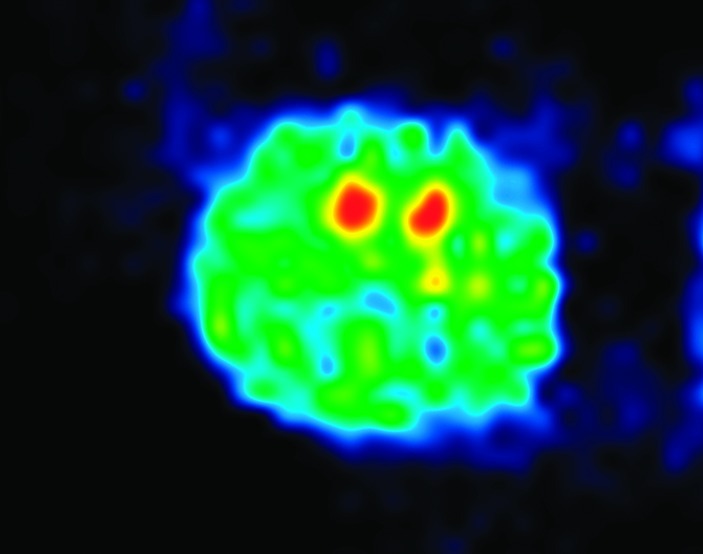

The table of contents graphic represents a positron emission tomography (PET) picture of adenosine A2A receptors in rat striatum using 11C-TMSX, an A2A receptor antagonist. We thank Dr. Paul Acton and Carlos Cotto for performing the PET experiments.